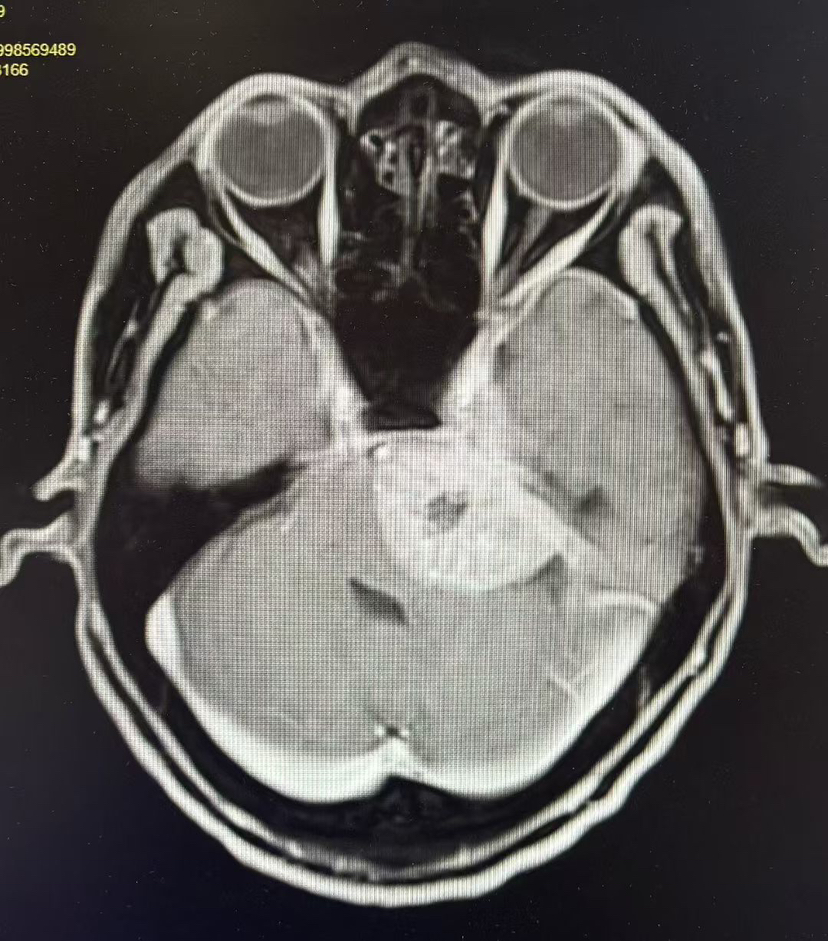

【“佟”话脑血运】佟志勇教授:大脑中动脉M1中段解离性动脉瘤的外科治疗策略

佟志勇

前天14:14